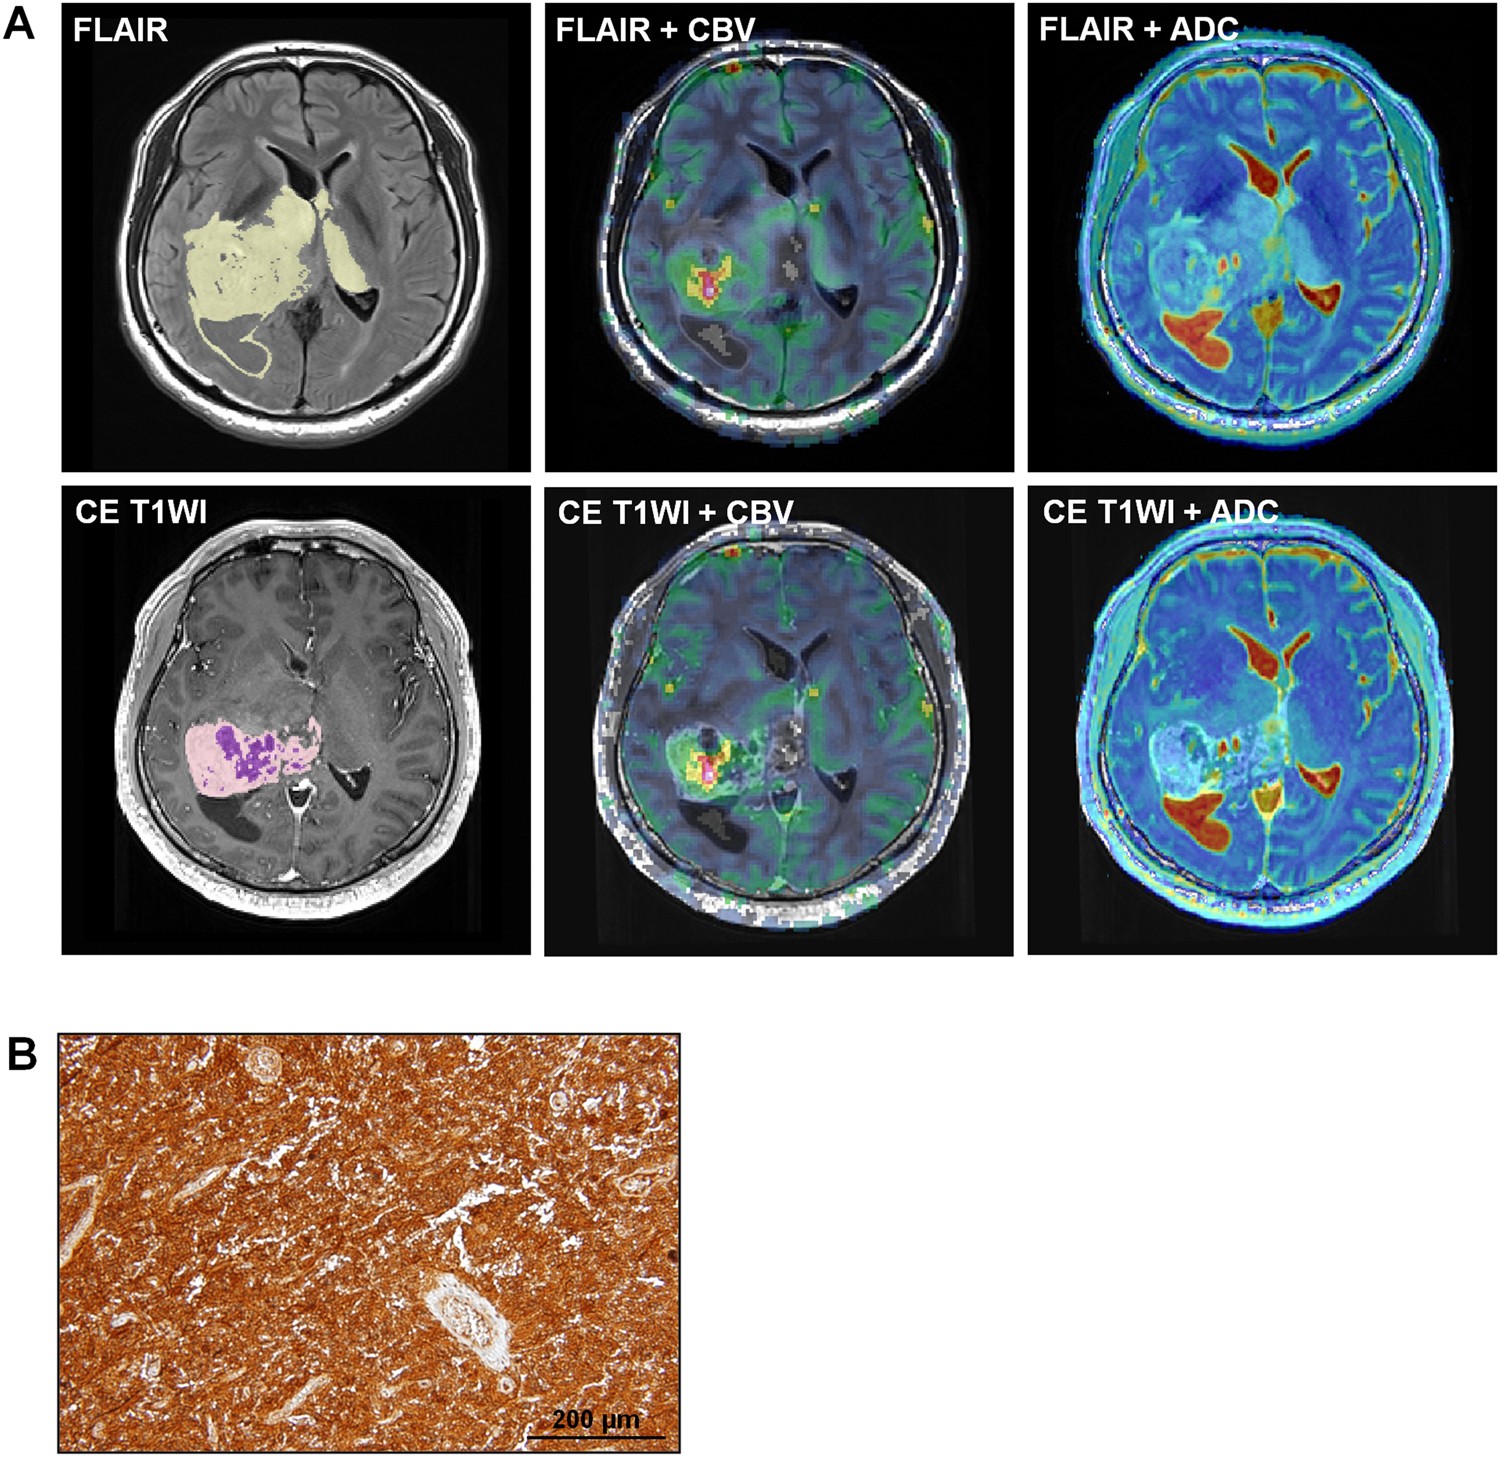

Figure 4

Images in a 42-year-old man diagnosed with GBM and a high level (204.9) of BCAT1 expression. (A) The tumor showed high nCBV and low ADC values from both FLAIR (Top line, mean nCBV: 6.86, mean ADC: 1211.26 × 10−6 mm2/sec) and contrast enhanced T1W1 (Bottom line, mean nCBV: 11.00, mean ADC: 1225.30 × 10−6 mm2/sec). The yellow and light purple ROIs indicate the entire tumor areas on FLAIR and CE T1WI, respectively, and the deep purple ROI represents the necrotic portion within the tumor on CE T1WI. (B) Histology showed a low level of BCAT1 expression.